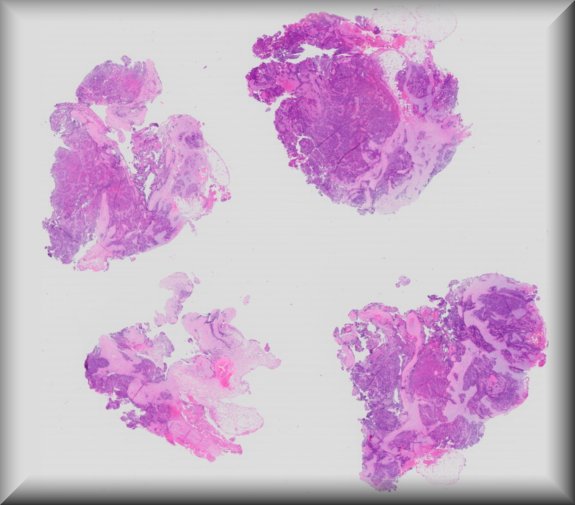

Nasreen A. Syed (Iowa city): Retinoblastoma |

|